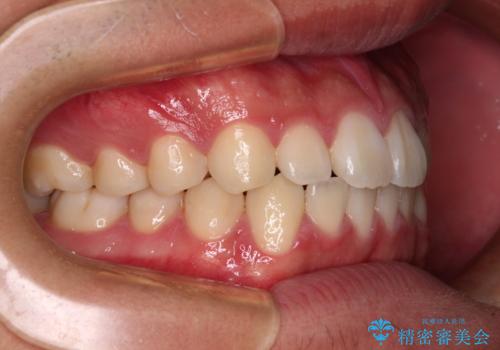

- 上下前歯の叢生を気にして来院された患者様です。

費用を抑え、期間もあまりかけずに治療をしたいとのことで、インビザライン・ライトを用いて矯正治療を行うこととしました。

インビザライン・ライトは、製作できるアライナーの枚数に制限があるため、移動可能な量に限りがあります。

一方で、半年から1年程度で治療を終えることができるため、軽度の歯列不正の患者様には大変お勧めです。